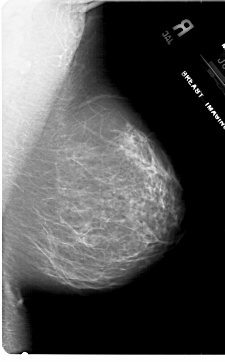

A_1787_1.LEFT_CC

LEFT_CC LINES 5641 PIXELS_PER_LINE 3796 BITS_PER_PIXEL 12 RESOLUTION 43.5 OVERLAY